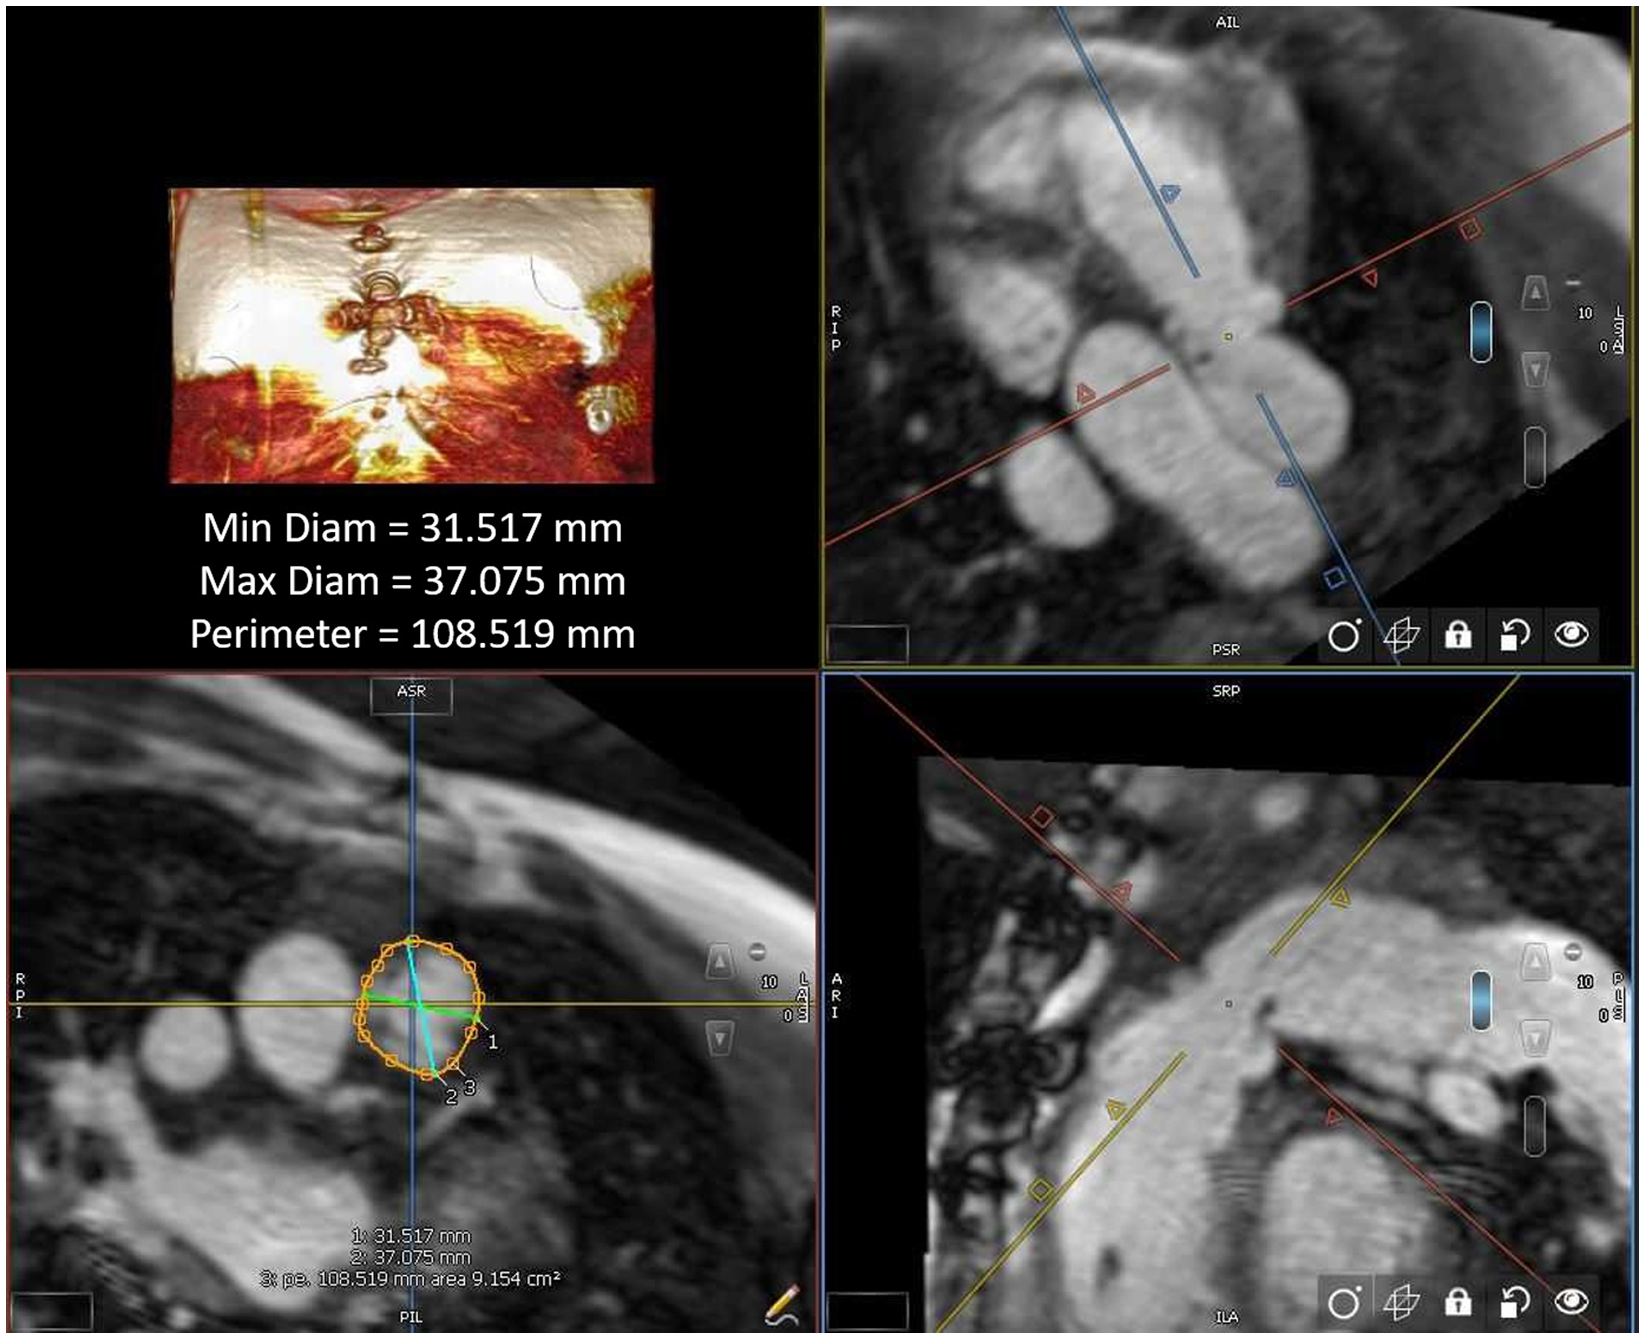

All MRI post-processing was performed blinded to clinical data by an image analyst with all analyses verified by a cardiologist (LEH) using CVi42 v. 5.13.5 (Circle Cardiovascular®, Calgary, AB, Canada). Ventricular volume and function were measured in the end systolic and end diastolic phase on SSFP cine images acquired in a short axis plane as a stack of 12 contiguous slices covering full length of both ventricles. The landing zone end-systolic (given that this represents the largest vascular dimension) perimeter and two orthogonal diameters were measured retrospectively in all study patients using multiplanar reconstruction by an imaging and interventional staff member (first author RAL and senior author LEH), agreeing on the intended valve site within the right ventricular outflow tract (Fig 1). The multiplanar reconstruction measurement was performed using non-contrast MRI sequence (whole heart) or a Twist sequence. The perimeter measurements were all calculated into a “circularised” diameter – derived via measurement division by π. Additional MRI parameters and cardiac catheterisation results (including right ventricular outflow tract balloon sizing and/or transcatheter pulmonary valve replacement procedures) were collected retrospectively for data analysis.

Figure 1. Right ventricular outflow tract measurement by cardiac MRI.